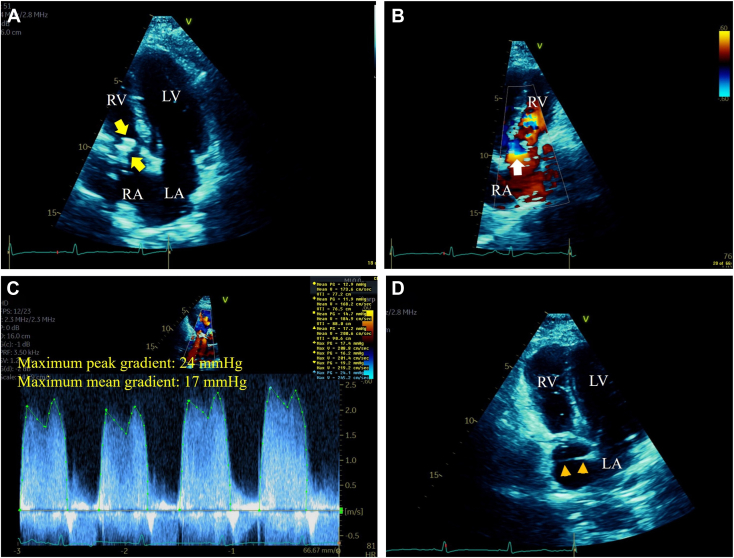

A TTE was performed to evaluate the reported cardiac mass and revealed a large RA mass moving inferiorly into the TV inflow during diastole, causing inflow obstruction as supported by turbulent color-flow Doppler at this level and severely elevated maximum peak and mean gradients of 24 mm Hg and 17 mm Hg, respectively, by color-flow-guided continuous-wave Doppler (Figure 2, Videos 1 and 2). Right atrial dilatation and bowing interatrial septum (IAS) into the left atrium (LA) indicative of elevated RA pressure were noted. The right ventricular (RV) size and function were normal, the estimated RV systolic pressure was 25 to 30 mm Hg, and the left heart appeared normal. Of importance, a membrane-like structure was noted traversing the RA cavity from the lateral wall to the distal IAS suggestive of a CTD (Figure 2).

Figure 2.

(A) Two-dimensional TTE, apical 4-chamber view, during mid-diastole, demonstrates a large (2.5 × 1.5 cm), elongated, irregular, and hyperreflectant RA mass moving inferiorly into the TV inflow (arrows). (B) Two-dimensional TTE, reversed apical 4-chamber view with color-flow Doppler during late diastole, demonstrates nonturbulent flow within the RA cavity, in contrast to turbulent flow with a convergence zone (arrow) at the TV inflow level caused by the obstructive RA mass. (C) Two-dimensional TTE, short-axis view, color flow–guided continuous-wave Doppler, demonstrates severe TV inflow obstruction with maximum peak and mean gradients of 24 mm Hg and 17 mm Hg, respectively. (D) Two-dimensional TTE, apical 4-chamber view, during early systole, demonstrates a membrane traversing the RA cavity from the lateral wall to the IAS (arrowheads) suggestive of a CTD. LV, Left ventricle; RV, right ventricle.